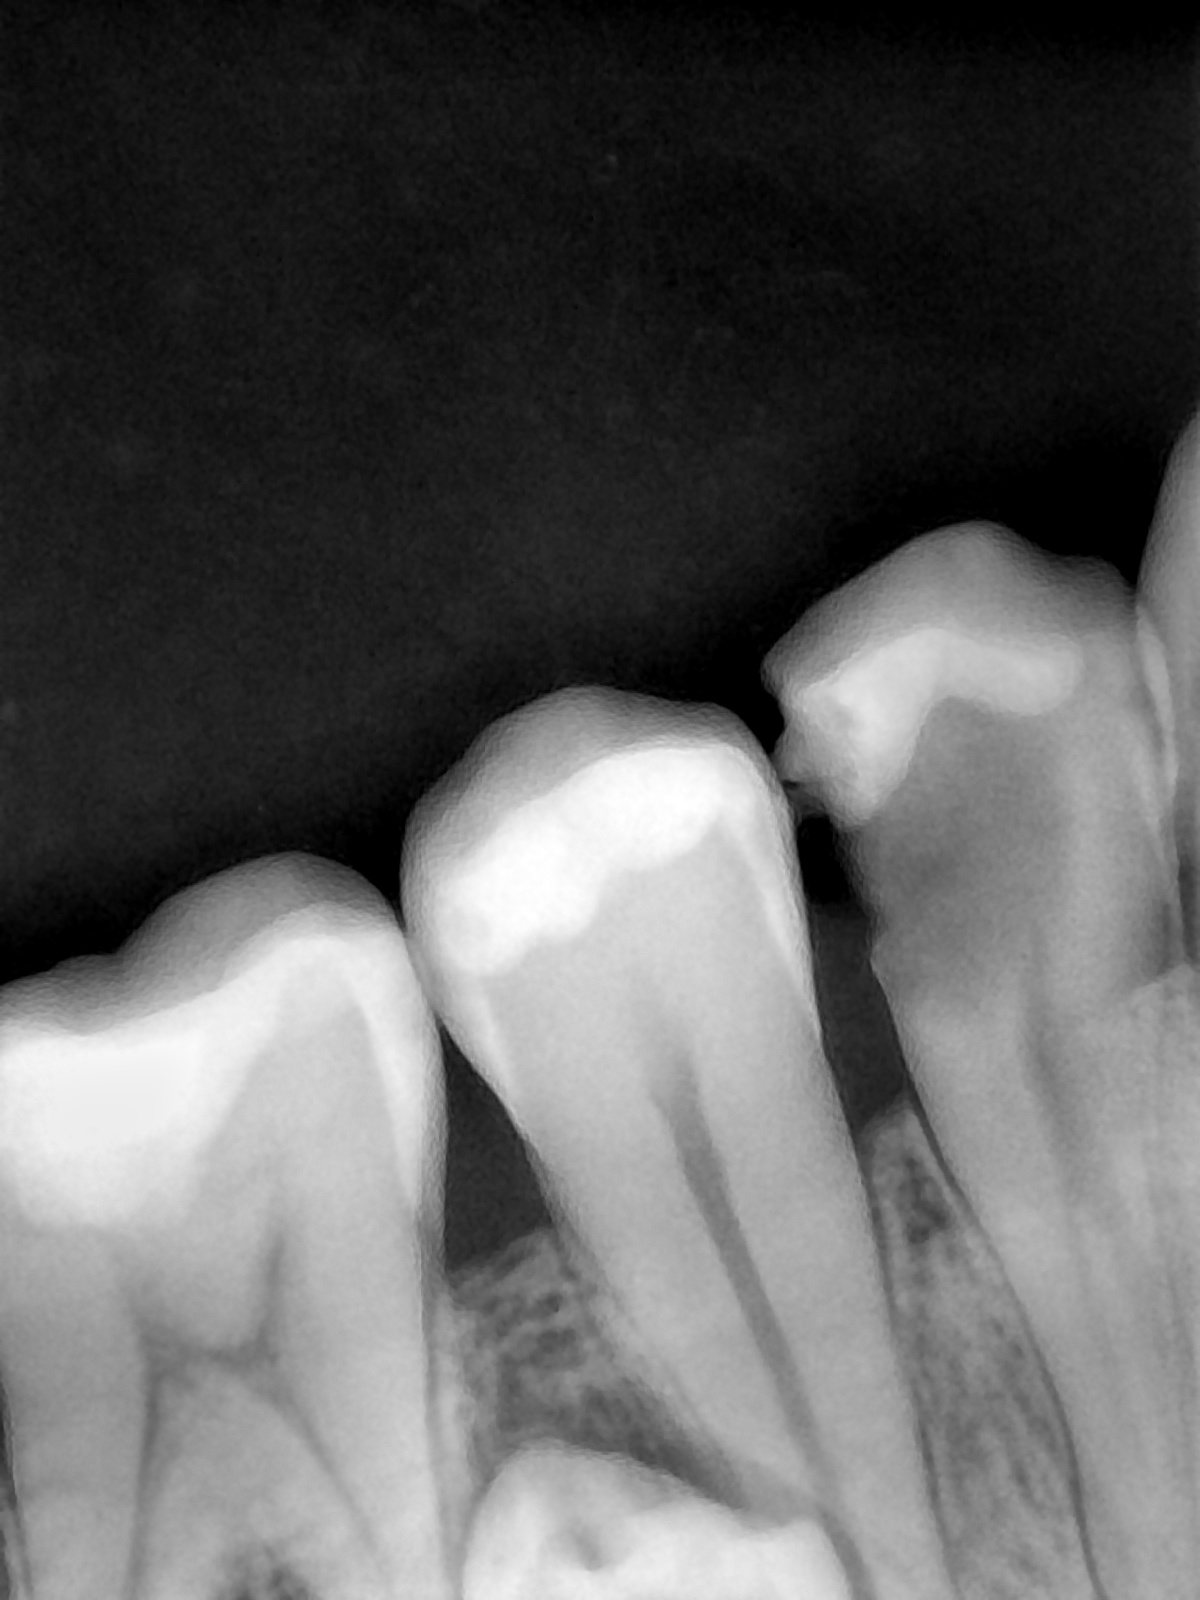

CR/DR 牙齿分割阶段记录

当前进展

- 完成了 CR/DR 牙齿相关分割训练

- 当前结果已经达到阶段预期,但仍有细节问题需要继续处理

相关测试

遇到的问题

- 训练过程中出现过 mask 下移问题

- 部分结果会出现 box 填充异常

- mask 边缘仍然有比较明显的锯齿感